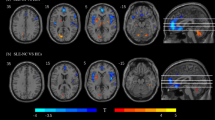

DiFrancesco MW et al. (2007) Functional magnetic resonance imaging assessment of cognitive function in childhood-onset systemic lupus erythematosus: a pilot study. Arthritis Rheum 56: 4151–4163